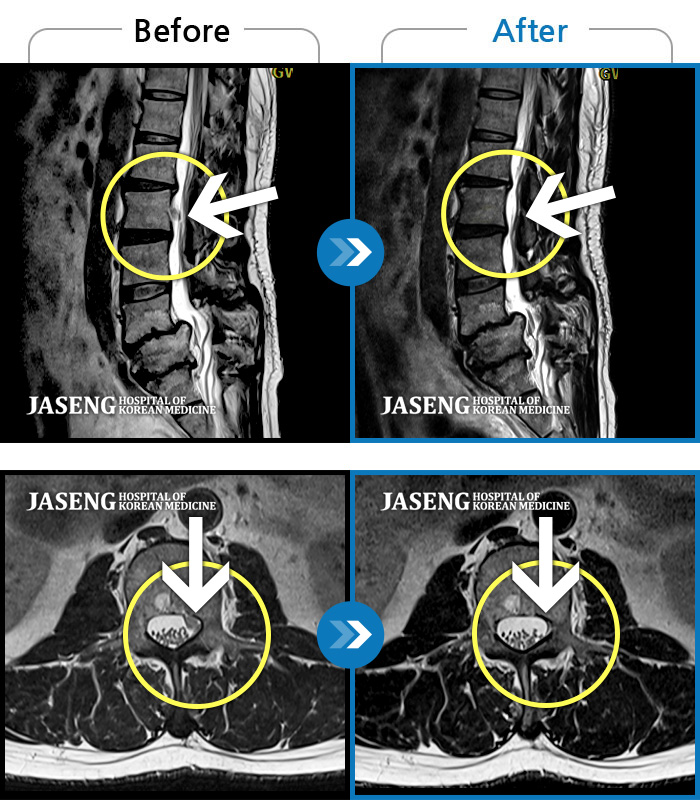

Before

After

양측 허리 통증과 좌측 허벅지부터 발바닥까지 송곳으로 찌르는 듯한 통증 지속되어 내원하셨습니다.

2023.12.26 ~ 2024.12.05